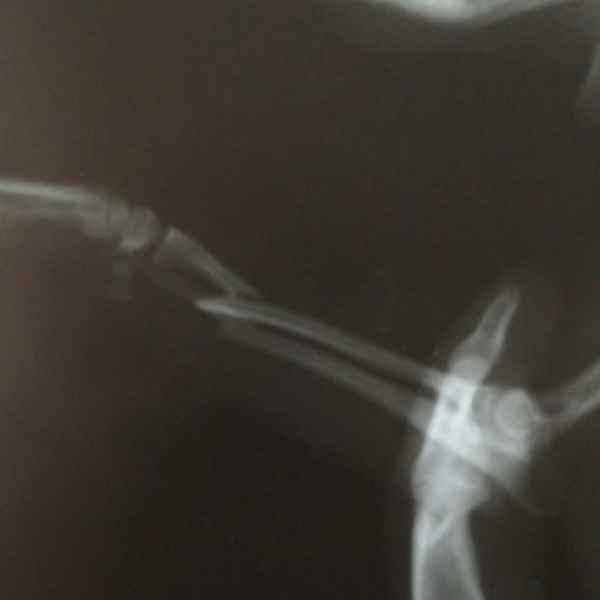

Этот пациент поступил к нам с кусаной раной левой грудной конечности После рентгенологического исследования обнаружили перелом костей предплечья. Сложность операции заключалось в том, что дистальный отросток лучевой кости был очень коротким. Хирургом нашей клиники было принято решение установить блокируемую lcp пластину. В данный момент пациент полностью восстановился..